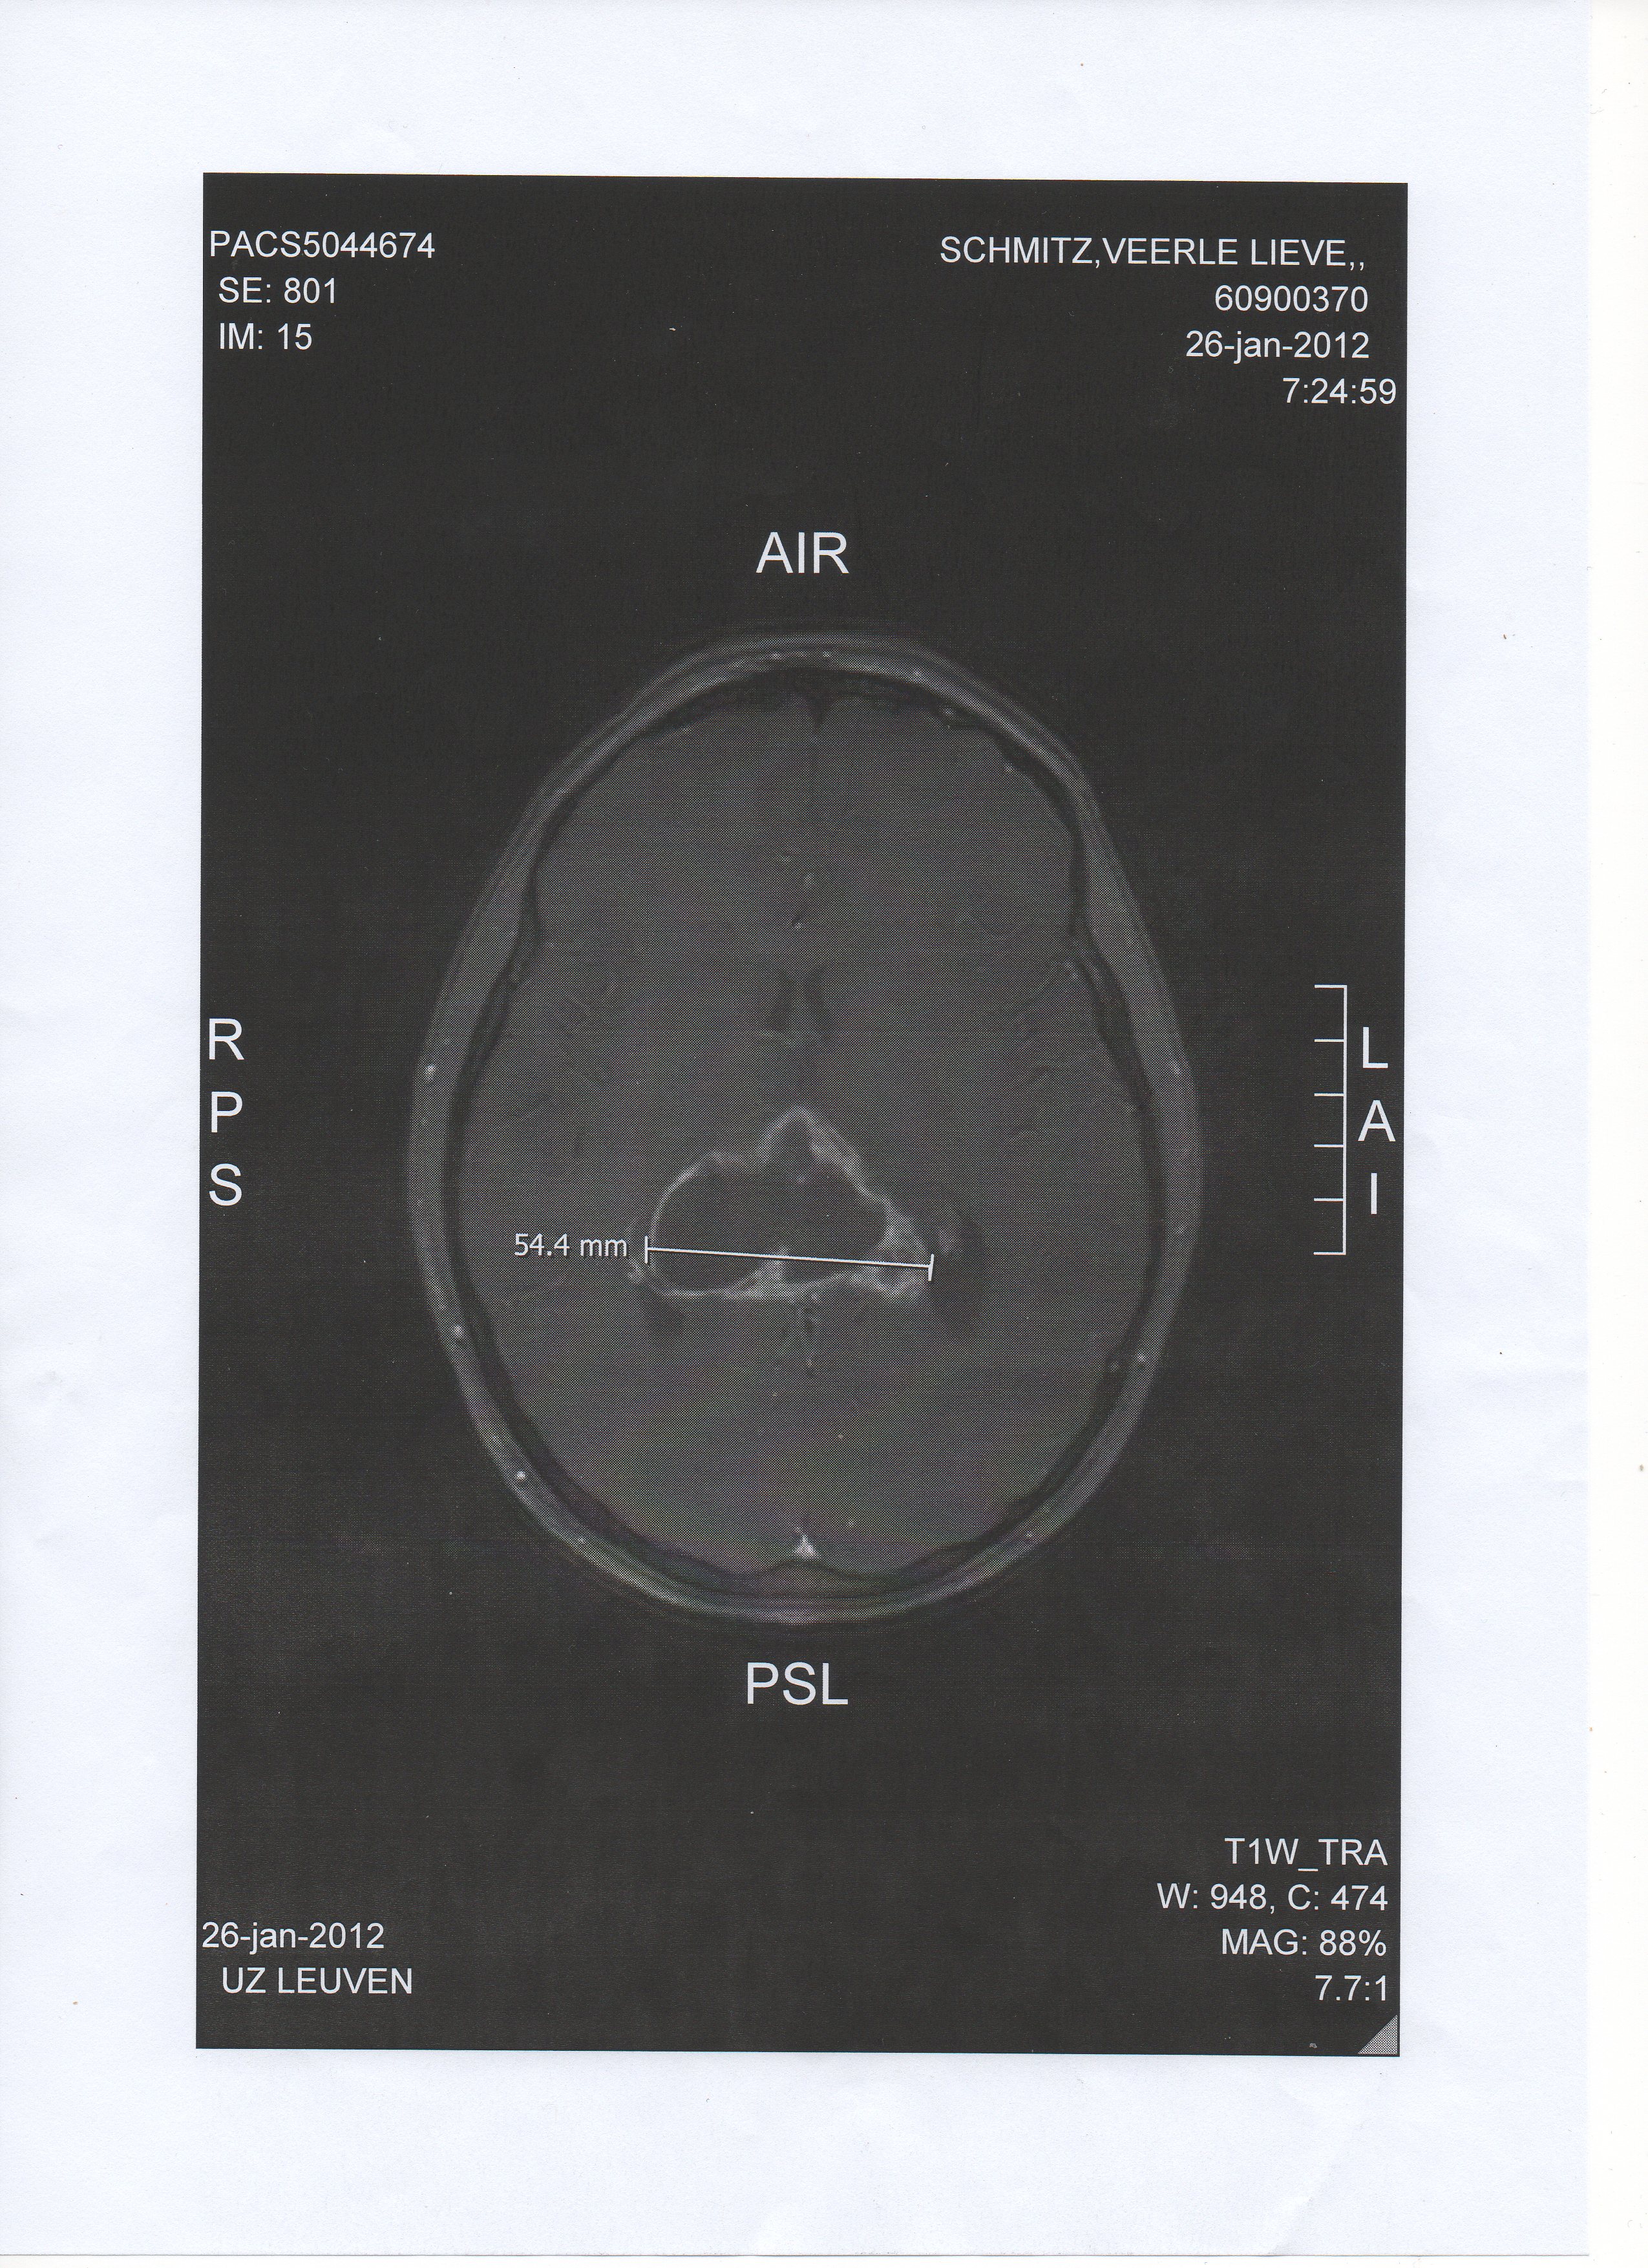

De tumor bevindt zich bij Veerle aan de onderkant van de hersenbalk en de bovenkant van de derde ventrikel. Hij lijkt verder uit te groeien naar de voorkant van de hersenbalk (van truncus naar splenium toe). De tumor heeft twee grote cystes gevormd, elk met een volume ter grootte van 2 eetlepels. Er is vernauwing van de aquaductus, het kanaal naar de vierde ventrikel. En ook groei naar de twee laterale hersenkamers of ventrikels (eerste en tweede ventrikel.) Naar het einde toe (vanaf augustus 2012 en dan veel sneller vanaf october 2012) gaat de tumor verder langs de hersenstam en zo naar de ruggegraat.

Veerle heeft haar vijand altijd willen kennen. Als er vrienden kwamen, dan liet ze hen de foto's zien van de tumor. Ik wil weten waar ik mee te maken heb.

De tumor in januari 2012De tumor in januari 2011